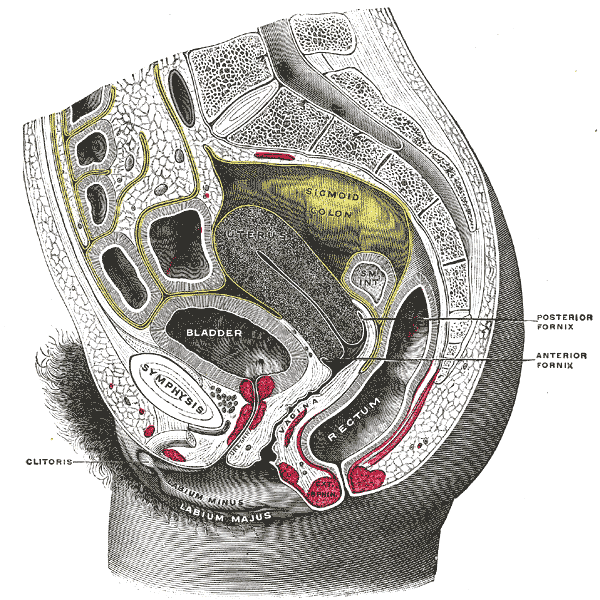

II. Anatomy

Uterus

- Pear shaped, thick walled muscular organ that is posterior to the bladder and anterior to sigmoid colon.

- Positions include:

- Anteverted – Most common position. The uterine fundus pointed toward the anterior abdominal wall.

- Retroverted – Uterine fundus pointed toward the spine. Can make transabdominal imaging more challenging.

Fallopian Tubes and Ovaries

- Fallopian tubes extend laterally from the body of the uterus toward the broad ligament.3

- Ovaries are attached to the uterus by the ovarian ligaments and to the lateral sidewall by the suspensory ligaments of the ovary.

- These are not rigid ligaments so ovarian position can be different

- Illustration 1. Sagittal view of pelvis. Image reproduced from Gray’s Anatomy. (Source: https://en.wikipedia.org/wiki/Vaginal_fornix#/media/File:Gray1166.png)